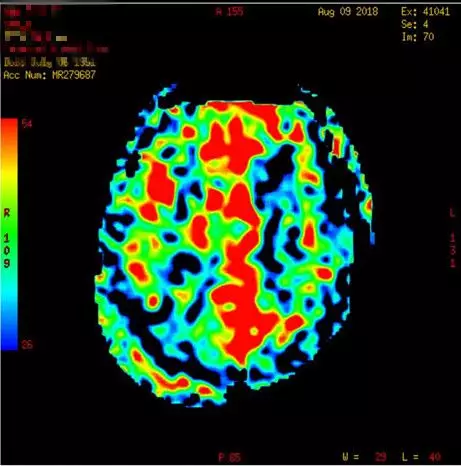

术后头颅MRI及ASL(08-09日 06:55分)